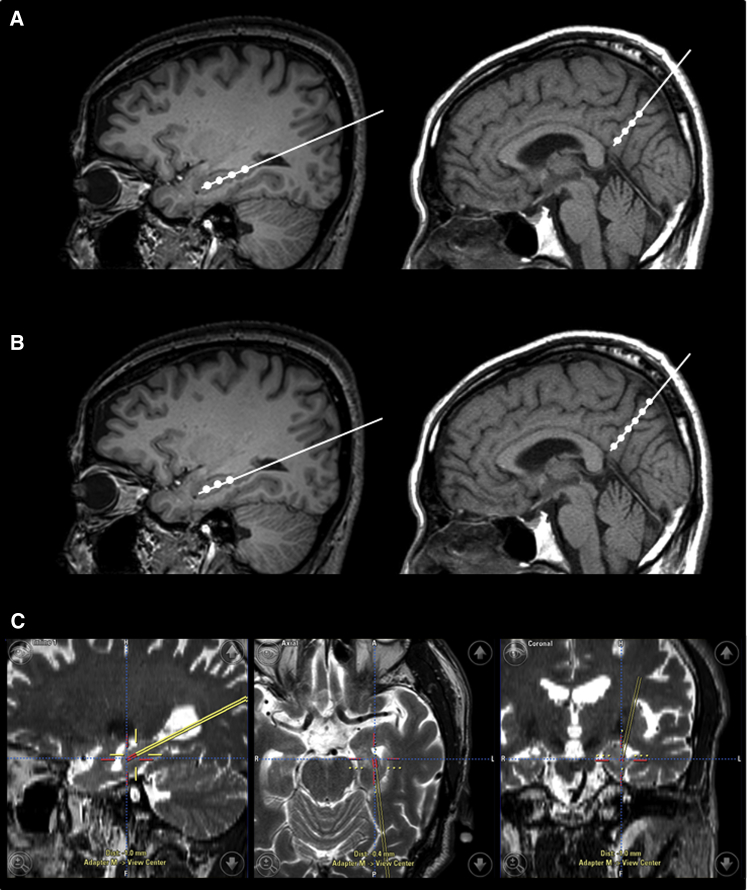

臍帶間充質干細胞的立體定向給藥

- (A)術中導航引導 hUCB-MSC 立體定向給藥。在縮回套管的同時,沿插入軌跡將 hUCB-MSC 注射到左右海馬和右楔前葉的四個部位(間隔 5 毫米)

- (B)然而,在九名患者中,有六名患者的第四次注射位于側腦室顳角,這可能是由于海馬嚴重萎縮所致。在這些情況下,省略的劑量被注射到右楔前葉,導致每個海馬有三個注射部位,右楔前葉有六個注射部位。

- (C)將 hUCB-MSC 立體定向注射到左海馬的示例